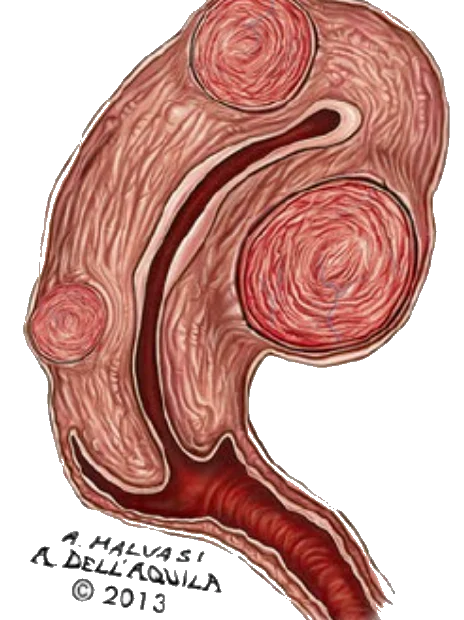

Önemli sayıda kadın, miyomlarının neden olduğu semptomları, sıradan regl ağrıları, stres, yaşlanma süreci … diğer faktörlere bağlayabilirler. Bu nedenle semptomları miyoma bağlamak yerine, farklı açıklamalar bulmaya çalışabilirler. Buda büyük veya rahimi tamamen sarmış (patates çuvalı) miyomatozis uteri (miyomların uterusu sarması – doldurması) durumuna evrilebilir.

Miyomlar, doğurganlık üzerinde etkisi olabilecek faktördür. Büyümüş miyomlar uterus içindeki embriyonun implantasyonunu (yerleşmesini – yuvalanmasını) engelleyebilir, sperm ve yumurtanın buluşmasını zorlaştırabilir.

Submukozal miyomlar ve fertilite:

Submukozal miyomlar, döl yatağına yerleştiğinden doğurganlık üzerinde daha fazla etkiye sahip görülebilir. Bu tür miyomlar, implantasyonu engelleyebilir, gebelik sırasında komplikasyonlara olasıdır.